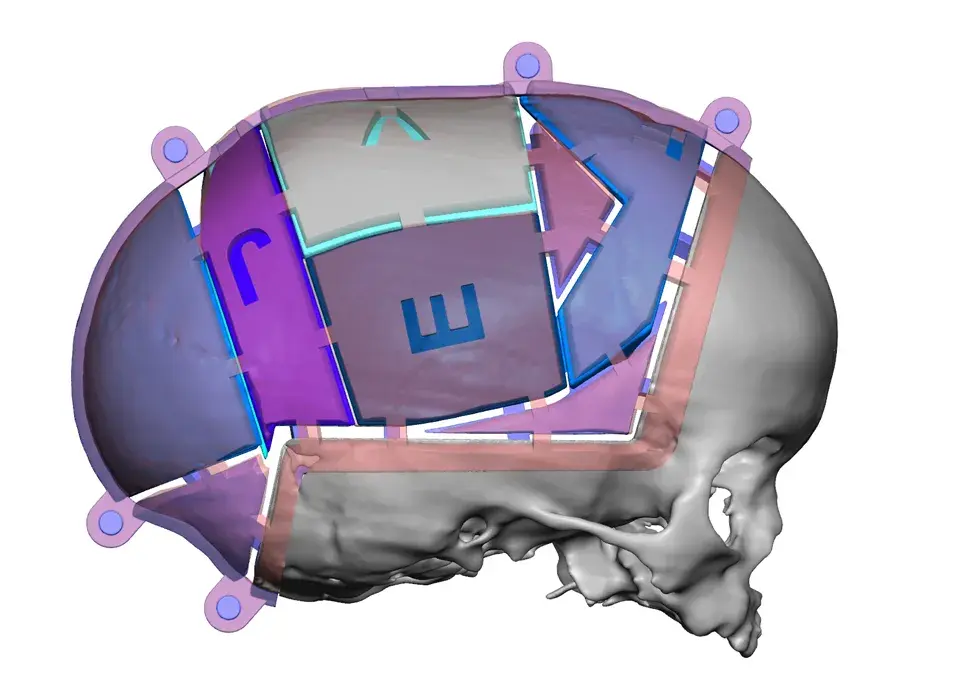

3D Systems' VSP® surgical planning solutions for craniomaxillofacial (CMF) applications received FDA clearance as a service-based approach to personalized surgery over 10 years ago.

3D Systems and Stryker Corporation have partnered to provide surgeons with best-in-class products and services for craniomaxillofacial surgeries. As a leader in personalized healthcare solutions, 3D Systems has planned and delivered devices for more than 140,000 patient-specific cases. The Stryker Craniomaxillofacial business specializes in providing patient-specific options and innovative solutions that help drive efficiencies in surgical suites. The combination of Stryker’s specialized team and advanced implants with 3D Systems' cutting-edge 3D printing technologies and expert consulting services positions both companies to provide a superior level of service to healthcare professionals who use these revolutionary solutions.